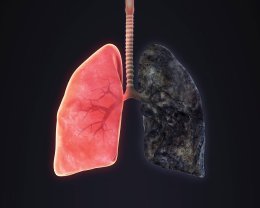

Учёные заявили, что лёгкие курильщика успешно восстанавливаются, даже если стаж курения был большим, но только если тот бросит курить. Это опровергает миф о том, что при большом стаже бросать уже не и...